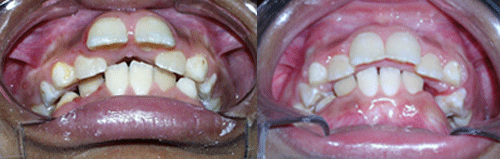

Protruded teeth (bucked teeth) happen when either the upper jaw is too far forward, the lower jaw is too far back, or a combination of both. Expert analysis allows us to determine the cause of the protrusion, and the most effective treatment plan.

With this type of bite, the front teeth are very protuded, and makes these delicate teeth highly prone to trauma, injury, and even premature tooth loss.

We have a number of different options and appliance types for correcting protruded teeth. The photos below illustrate protruded teeth, and the corrections in our patients.